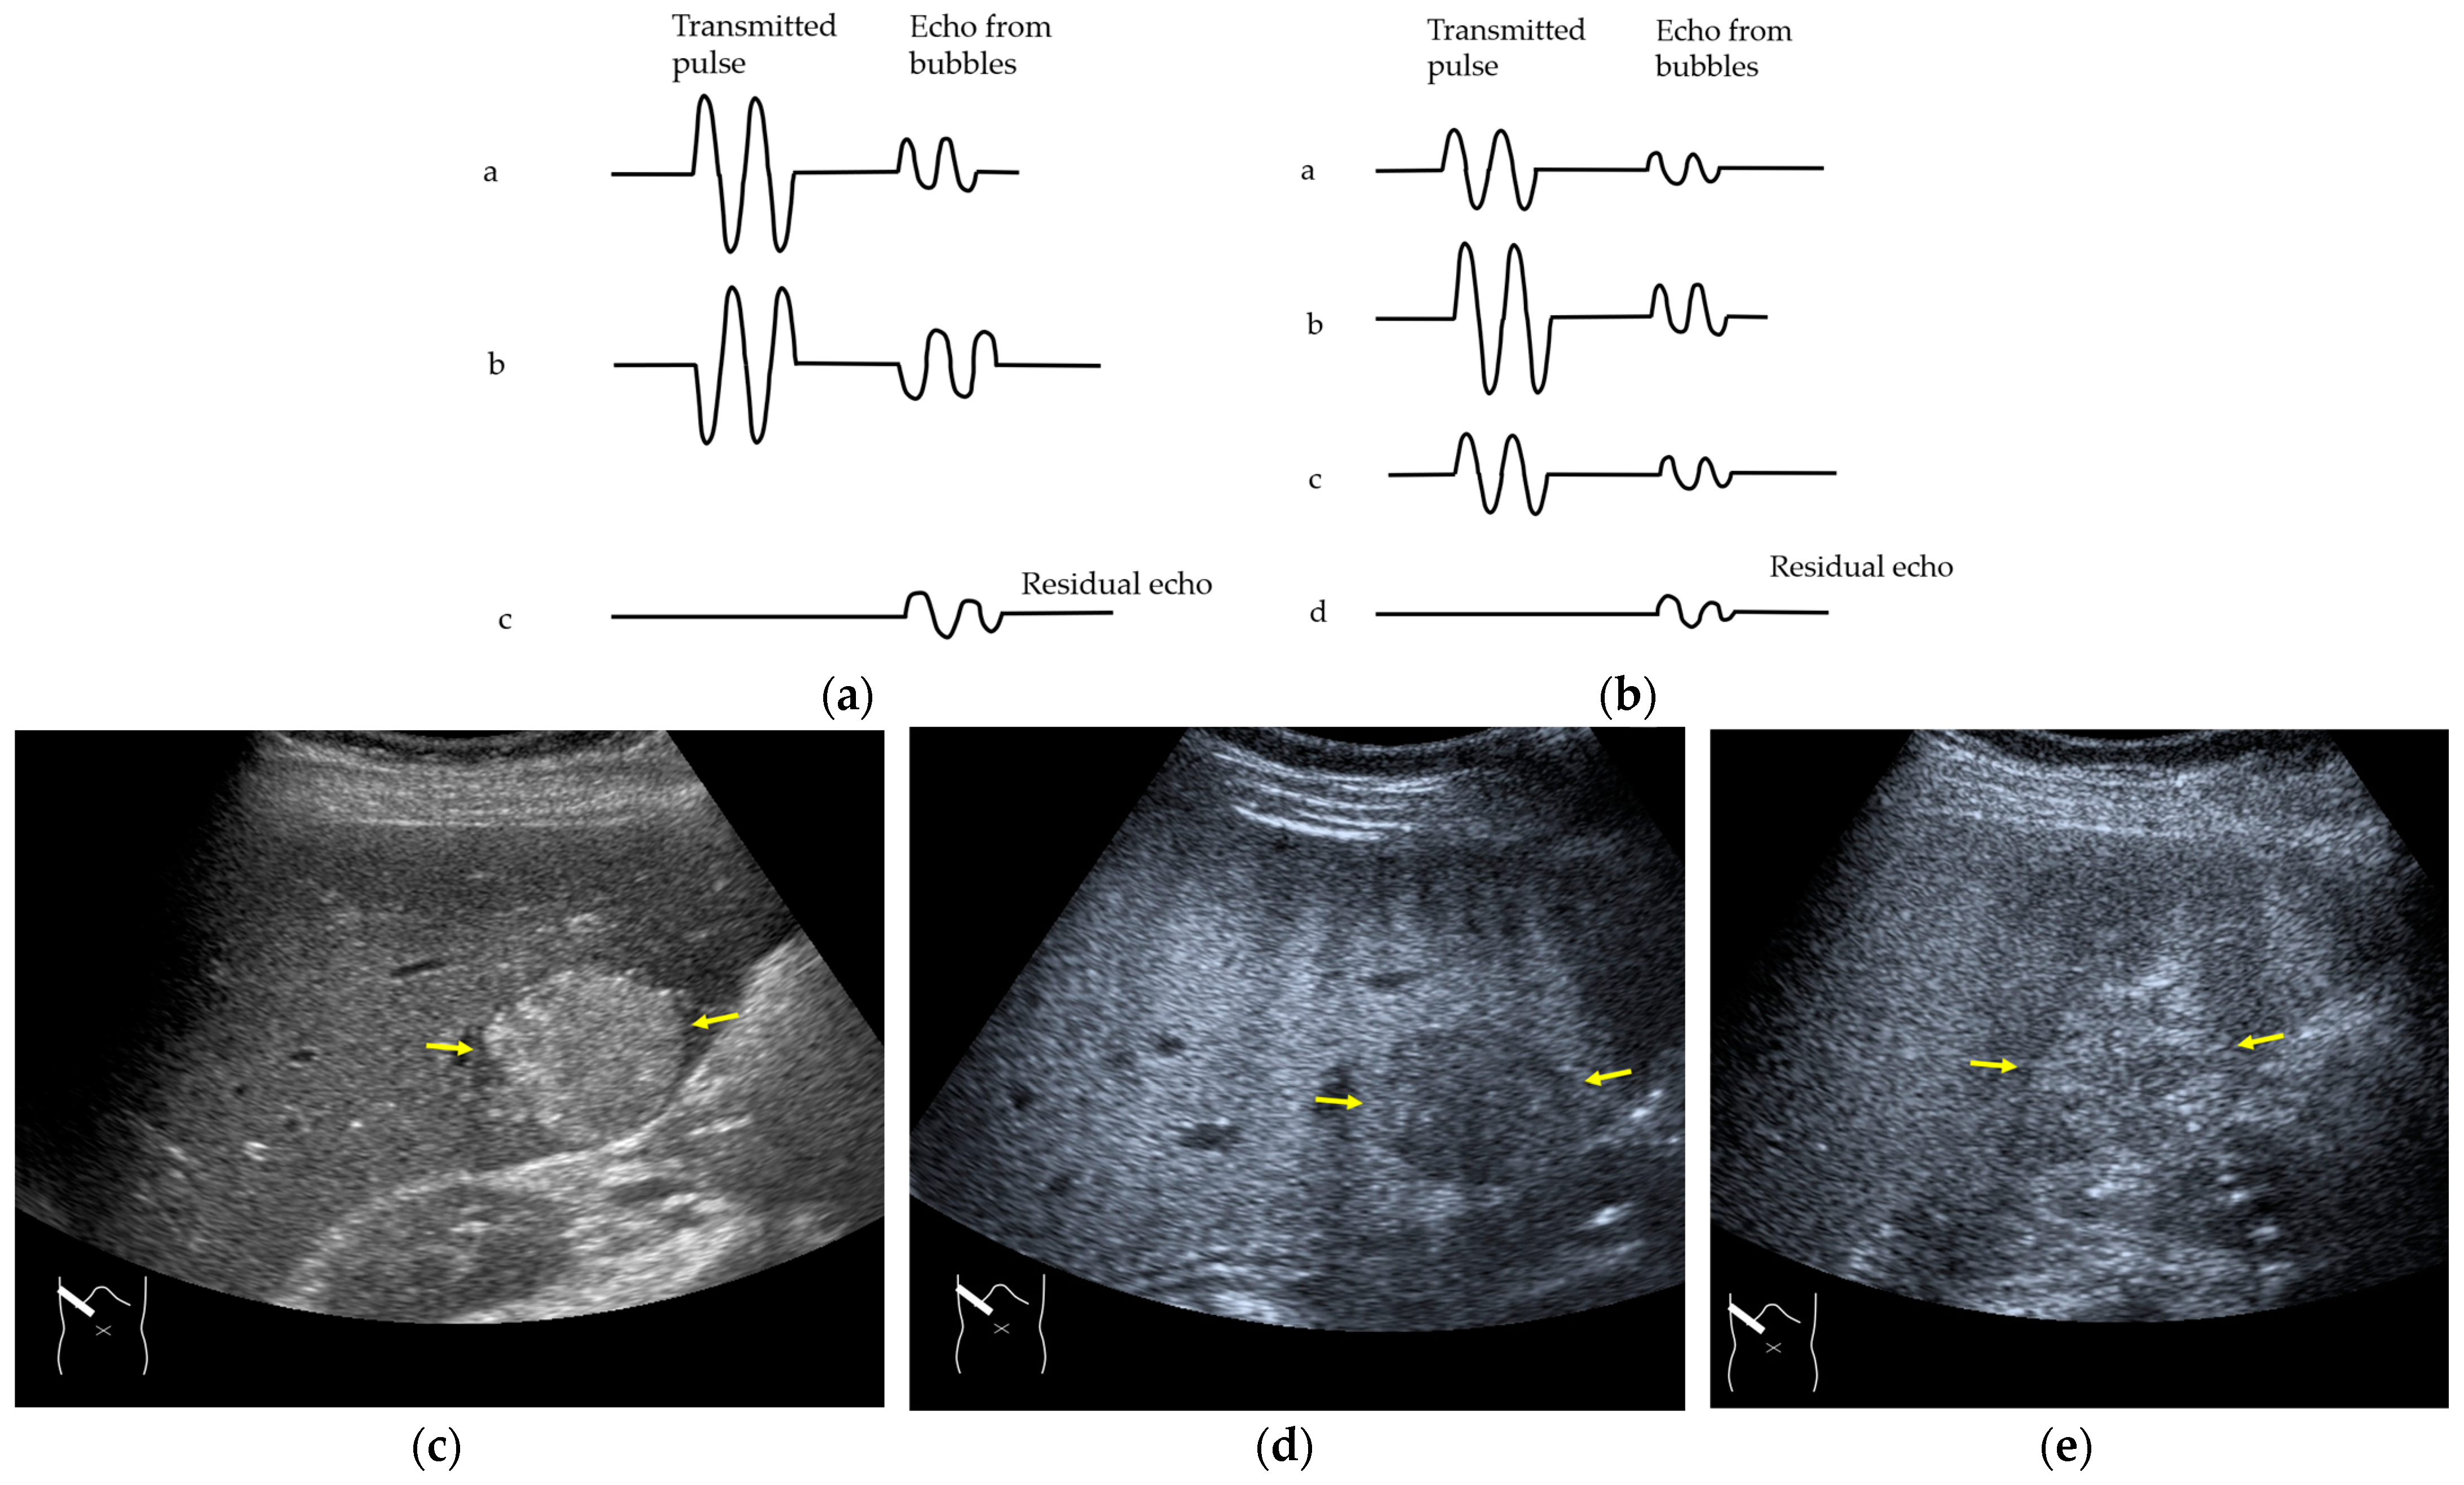

3.2.1. Microbubble Destruction Artifacts

Microbubble destruction occurs during daily CEUS examinations in all phases, even under the optimal settings. The most representative example is a microbubble destruction artifact seen at the hepatic surface (Figure 11). Thus, it is important to understand that inappropriately increased microbubble destruction occurs in the case of continuous CEUS examination, even under optimal settings. Bubble destruction artifacts cause a delicate diagnostic problem, especially when evaluating the degree of wash-out. Generally speaking, the degree of microbubble destruction differs from area to area depending on the blood flow velocity. We encounter this problem most frequently in hemangioma, where destroyed microbubbles are not quickly replaced in intrahemangioma sinusoids because of the low blood flow velocity within them [53], while destroyed microbubbles can be quickly replaced in the surrounding hepatic parenchyma (Figure 12). This phenomenon causes the important diagnostic problem of mimicking a malignant lesion. According to the CEUS LI-RADS 5) classification, the presence of wash-out in the later phase suggests the diagnosis of a malignant tumor in more than 90% of cases [2,11,12,13,14,15,16]. The simplest prevention strategy is the “re-injection” of a contrast medium [54], which enables us to observe the target lesion in all phases once more, from the arterial phase until the later phase, with intermediate scanning interruptions.

Figure 11.

Microbubble destruction artifact. (a) Gray-scale US of the liver surface shows no abnormality. (b) Although the M.I. of the examination is not very high, a long scanning time (approximately 15 s) causes an unintentional microbubble destruction artifact (arrows) at the hepatic surface.

Figure 12.

Manhole-like defect in hemangioma: (a) gray-scale US of the case (arrows: hemangioma); (b) CEUS shows a cotton wool appearance in the periphery of the lesion (arrows): (c) the lesion shows a complete defect in the lesion during observation (arrows); (d) a reasonable explanation of this phenomenon. In hemangioma, destroyed microbubbles are not quickly replaced because of the low blood flow velocity, mimicking a wash-out phenomenon.